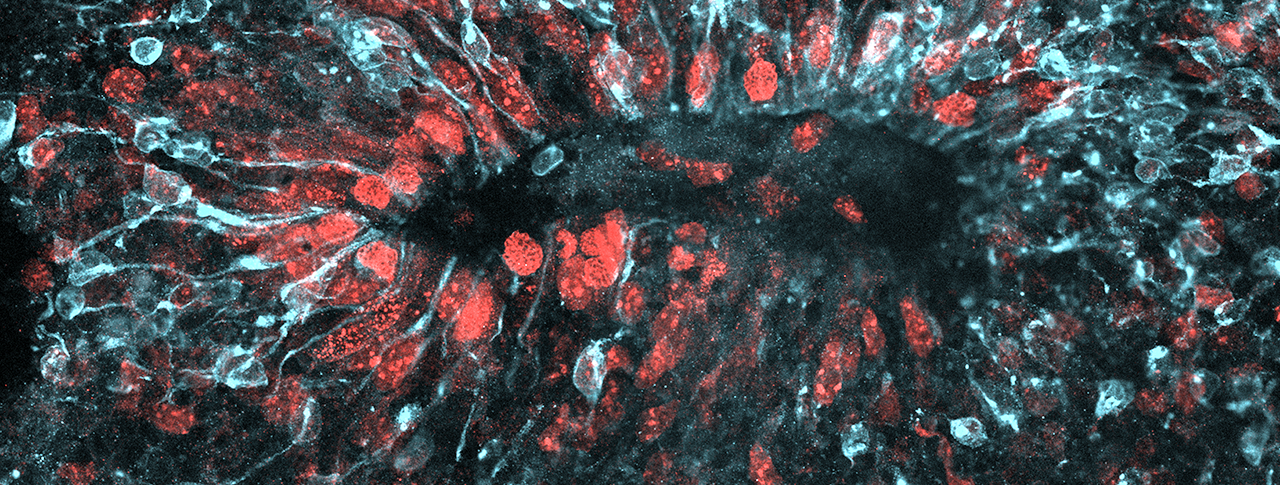

Main image: Zika virus (light blue) spreads through a three-dimensional model of a developing brain. Image by Max Salick and Nathaniel Kirkpatrick/Novartis

Working in a facility dedicated to infectious disease research, the scientists exposed two-dimensional cell cultures of AXL-knockout human NPCs to the Zika virus. They followed up by exposing three-dimensional mini-brain “organoids” containing such NPCs to the virus. In both cases, cells clearly displayed Zika infection. This finding was supported by an earlier study that knocked out AXL in the brains of mice.

“We knew that organoids are great models for microcephaly and other conditions that show up very early in development and have a very pronounced effect,” said Kaykas. “For the first few months, the organoids do a really good job in recapitulating normal brain development.”